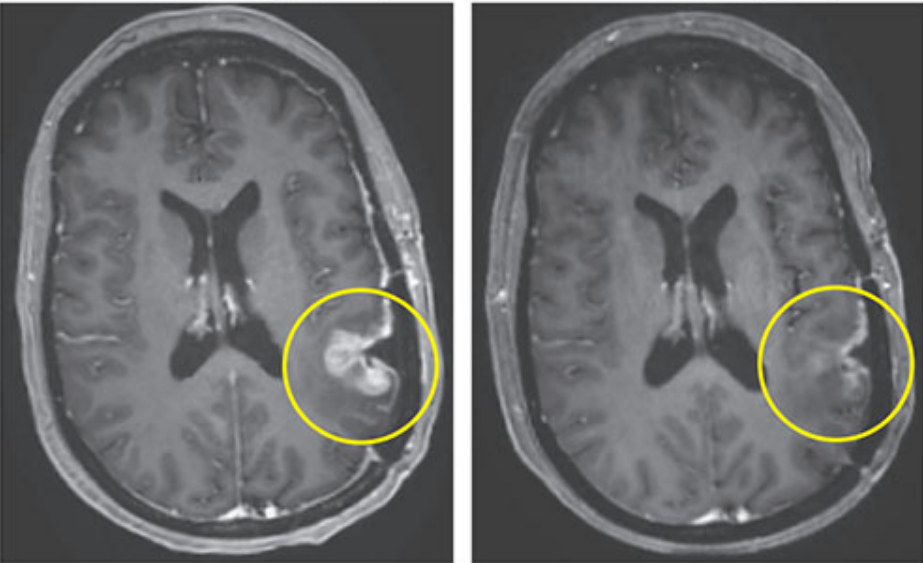

Lo sorprendente es que con una sola dosis administrada directamente en el cerebro, se lograron reducciones significativas del tumor en los primeros pacientes. La resonancia magnética evidenció regresión casi total en uno de ellos, mostrando cómo un nuevo tratamiento contra el cáncer ayudó a mujer de forma tangible. Esta rapidez marca un cambio en la manera de enfrentar el glioblastoma desde el sistema inmunológico.